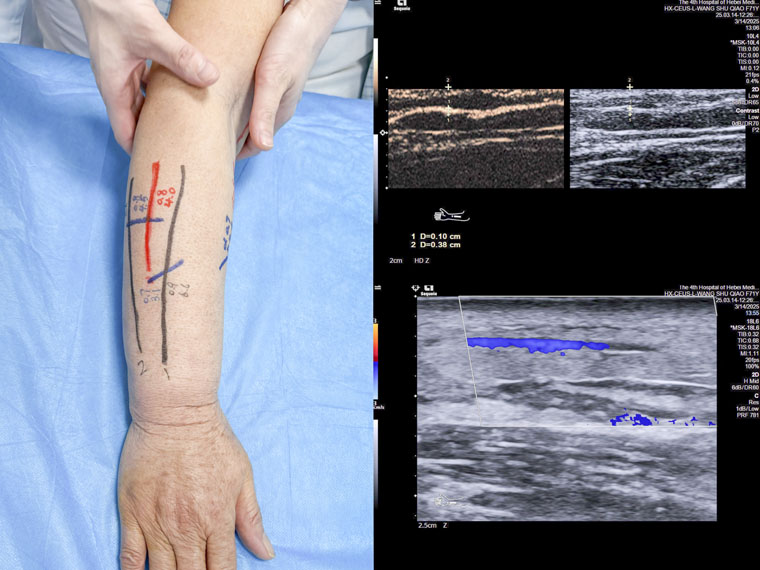

淋巴水腫患者術前定位的體表標記和超聲造影的圖像

在本次操作中,我院超聲科殷兆麟主治醫師協同科室負責人紀曉惠主任醫師為一名乳腺癌術后淋巴水腫患者進行上肢淋巴管超聲造影,診斷并評估淋巴管功能,精準識別有手術意義的皮下淋巴管及其鄰近微靜脈,并進行體表定位,助力我院乳腺中心完成河北省首例超聲造影輔助下的淋巴管靜脈吻合術。